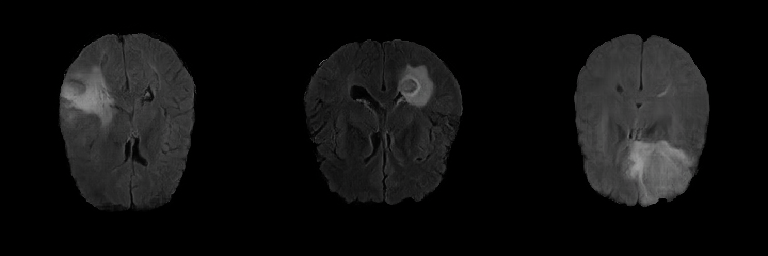

Generated Images Figure 5 shows the generated brain tumor FLAIR samples from -GAN-GP, PGGAN, and PGGAN-SSIM in AXI. The generated samples from all models look realistic and are close to the real images, where the white areas (Gliomas area) are concentrated and unified, indicating the training stability with gradient penalty. However, the samples from -GAN-GP are blurry, and the detailed brain features disappear since the loss of image information becomes serious when the image resolution increases in -GAN-GP. The generated samples from PGGAN and PGGAN-SSIM have clear and realistic brain features (FLAIR texture and tumor appearance) with diversity, which illustrates that PGGAN architecture is a well-suited model to generate brain MR images.